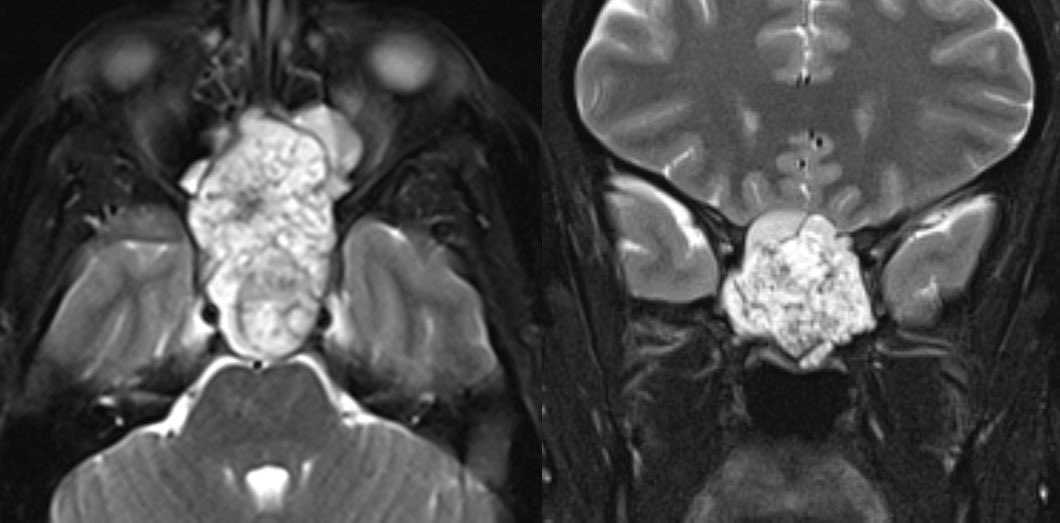

11 yo male with history of growth retardation and myopia presents with bradycardia and loss of consciousness.